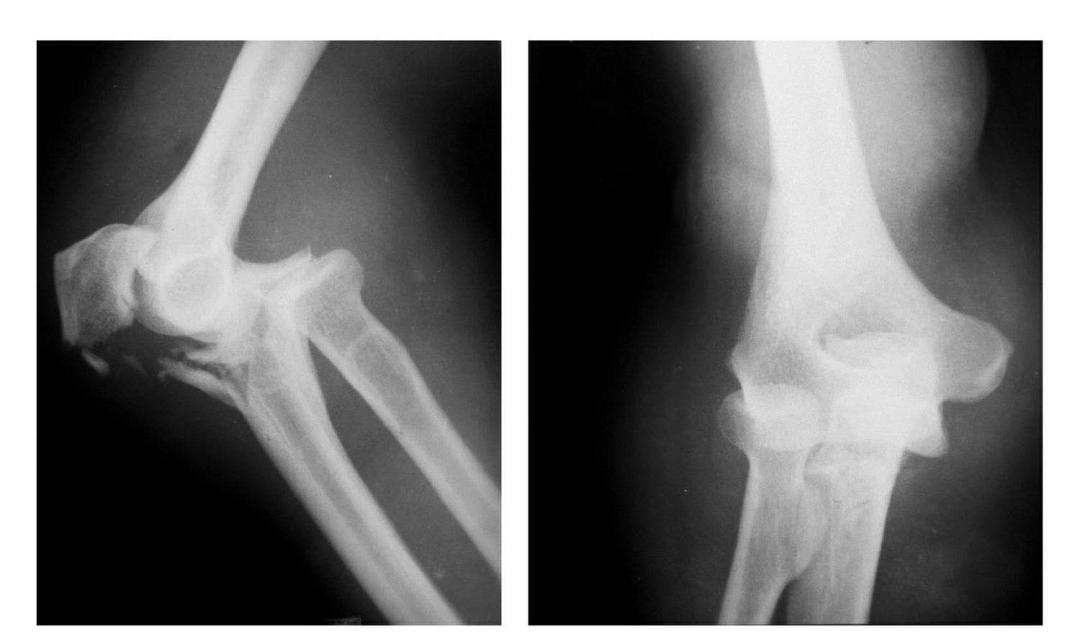

(二)部分骨折

本病亦称科-洛(Kocher-Lorenz)型骨折

例1:肱骨小头软骨面及其下方少量骨质呈“新月样”被剥脱,且向肘前上方移位并桡骨头前半部骨折。

例2:肱骨小头软骨面剥脱性骨折,致该小头新月状骨片被向前脱位的桡骨头顶向肘关节前上方,并尺骨干中段骨折(孟氏伸展型骨折)。